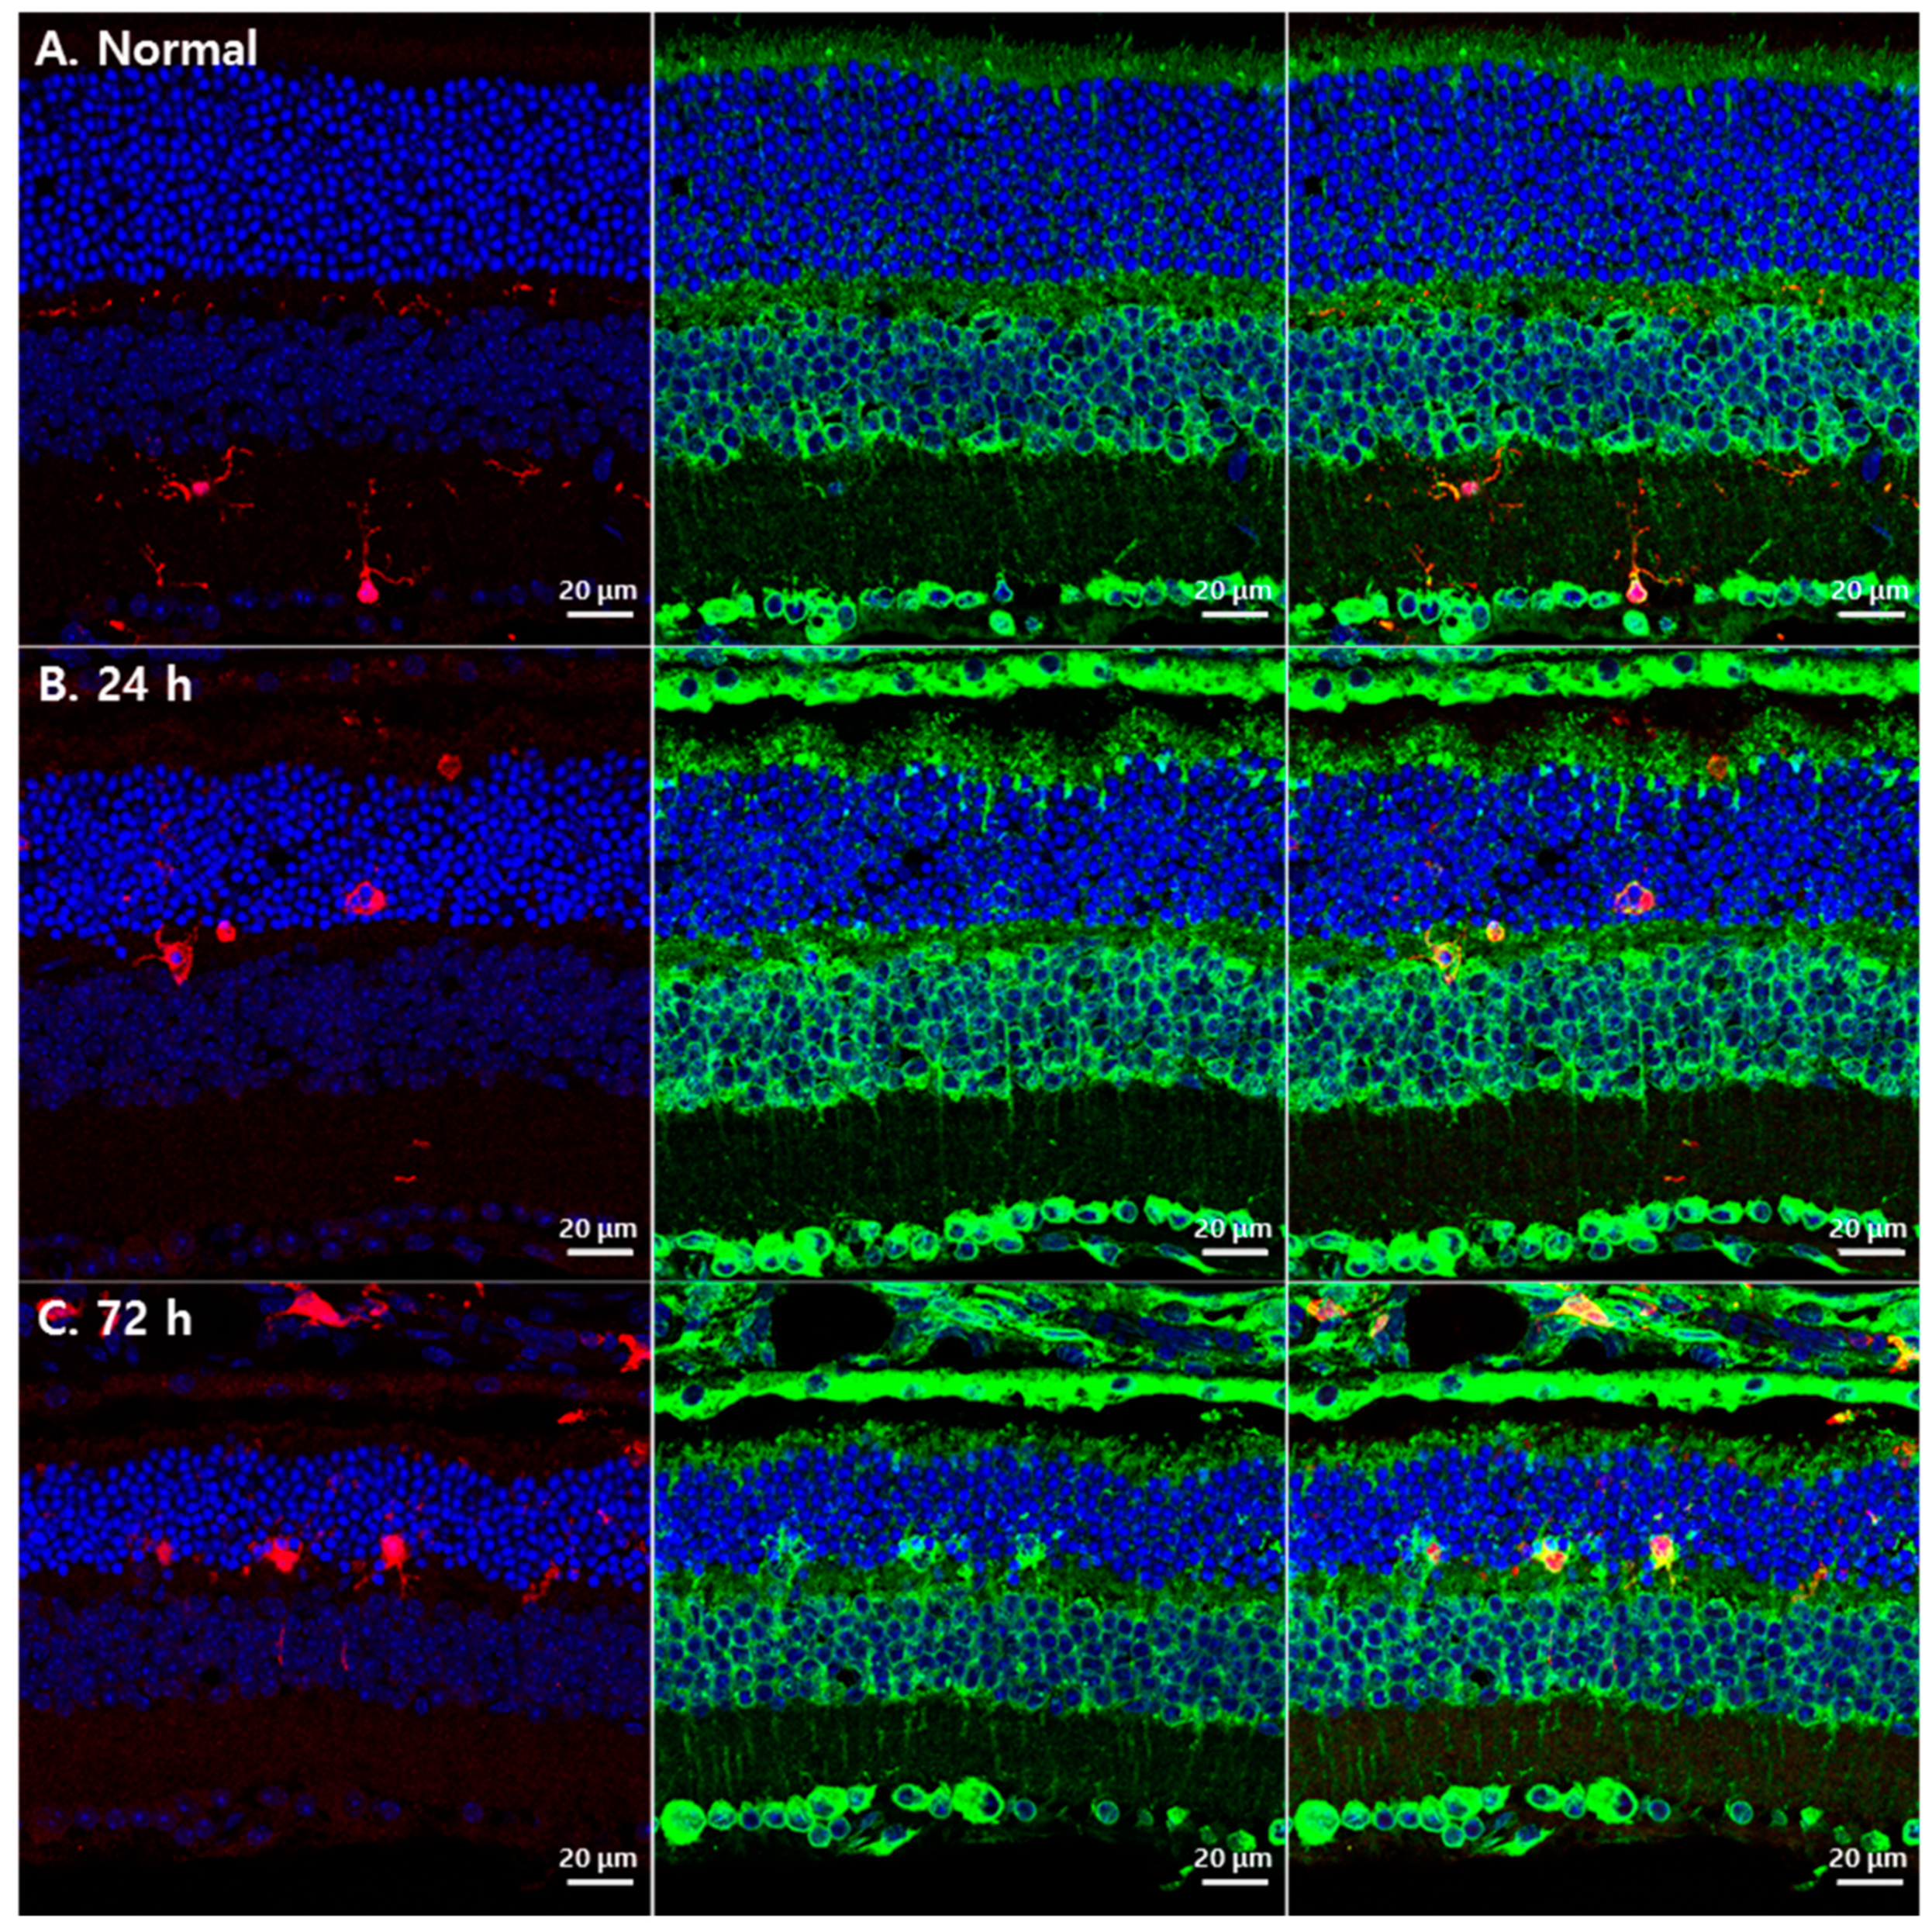

3.2. Changes in GRP78 Expression in Blue LED-Induced RD